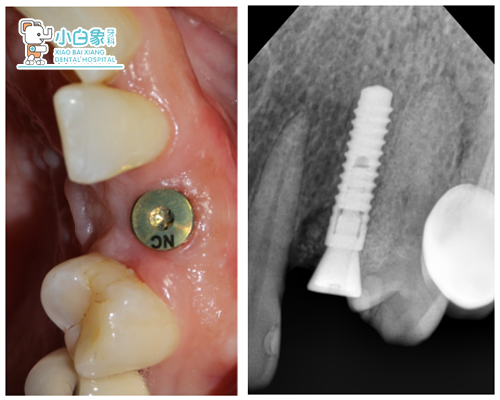

2017年11月4日 23见愈合帽暴露,取出愈合帽,测ISQ值:近颊、近舌、远颊、远舌、舌侧均为70,颊侧71,装转移杆,硅橡胶取模,上回愈合帽。比色:颈1/3,3M1,切2/3,3M2。

愈合帽

袖口 转移杆